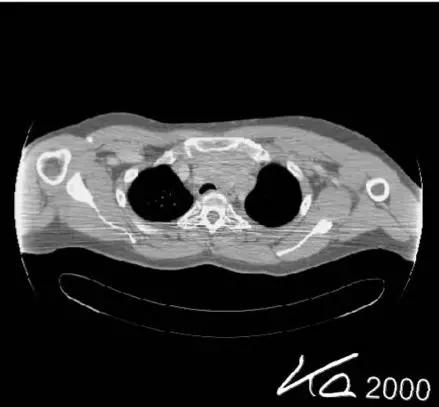

射线束硬化伪影:X线管发出的X线束是具有不同能量的连续的光谱,通过物体后光子能量的改变由该物质的衰减系数决定,而有效能量转移到高值一端的现象,称为“射线束硬化效应”。射线束硬化效应” 如果不能有效补偿,将会在图像中央产生环状或条状暗影。 抑制的方法是在焦点侧采取预滤过、软件校正。

(射线束硬化效应)